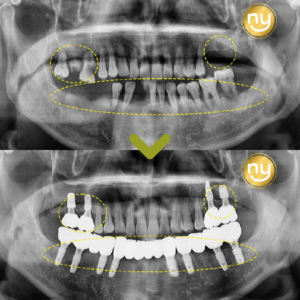

위 환자분은 충치가 많이 진행되어 신경치료한 치아를 사용하고 있었습니다.

하지만, 오랜 기간이 지나 치아 뿌리 끝에 염증이 생겨 발치를 권유받았는데요,

발치를 하더라도 치아 뿌리만 손상 없이 잘 살리면,

기존 치아를 살리는 치아재식술이 가능합니다.

위 환자분은 재식술에 성공해 신경치료 후,

염증을 해결하고 내 치아를 살려 사용할 수 있게 되었습니다.

시술 4개월 후에도 정기적으로 내원하셔서 구강 상태를 확인해

문제없이 유지 및 관리하고 있습니다.